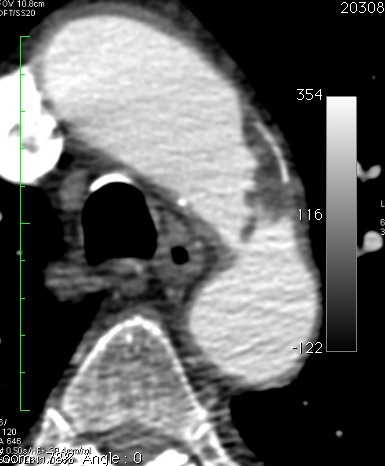

Ici, on trouve trois couches, une calcification pariétale, une plaque athéromateuse calcifiée, et un débris mobile (ou thrombus?), qui agite son drapeau en signe de victoire, ou de détresse (comme vous voulez!).

Pour des raisons mystérieuses, la plaque, qui paraissait calcifiée en échographie (hyperéchogène, cône d’ombre postérieur) est hypodense en scanner (seule la paroi externe est calcifiée).

Trois couches : un radeau en calcaire, des naufragés athéromateux, un drapeau en thrombus, ça ne vous rappelle rien?